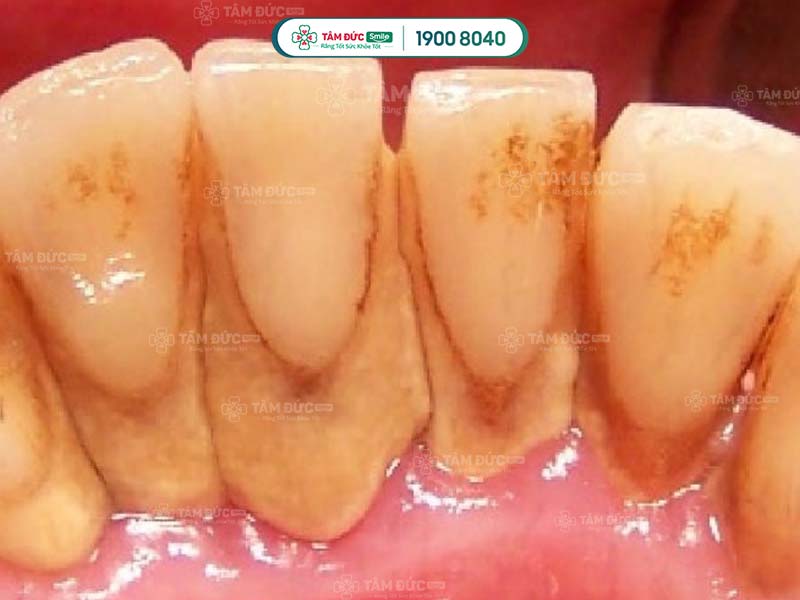

- Phát hiện có nhiều cao răng và mảng bám ở thân răng hoặc dưới nướu.

Cao răng không phải là nguyên nhân trực tiếp gây ra các bệnh lý về răng miệng, nhưng lại là nơi trú ngụ của nhiều loại hại khuẩn. Vì vậy, cao răng tạo điều kiện để vi khuẩn gây bệnh.

Cao răng tích tụ lâu ngày sẽ gây ra các bệnh lý như: Sâu răng, viêm nướu, tụt nướu, mòn men răng, viêm nha chu,... Do đó, cạo cao răng thường xuyên giúp Quý khách ngăn chặn vi khuẩn phát triển, giảm nguy cơ mắc phải các bệnh lý răng miệng.

Cao răng có màu sẫm, tích tụ trên thân răng làm ảnh hưởng đến thẩm mỹ nụ cười. Cạo cao răng giúp Quý khách loại bỏ các mảng bám tối màu, trả lại hàm răng trắng sáng và đẹp mắt hơn.

Vi khuẩn tích tụ trong cao răng thời gian dài sẽ tấn công vào sâu bên trong, làm hư hại răng và nướu nặng nề. Lâu dần, xương hàm của Quý khách có thể bị tiêu biến, tăng nguy cơ lung lay răng vĩnh viễn. Như vậy, cao răng nghiêm trọng có thể làm cho Quý khách đối mặt với vấn đề mất nhiều răng cùng lúc.

Để bảo vệ sức khỏe xương hàm và răng, Quý khách cần cạo cao răng định kỳ. Khi ngăn chặn được sự tích tụ của vi khuẩn, sức khỏe răng miệng của Quý khách sẽ ngày càng tiến triển tốt hơn.